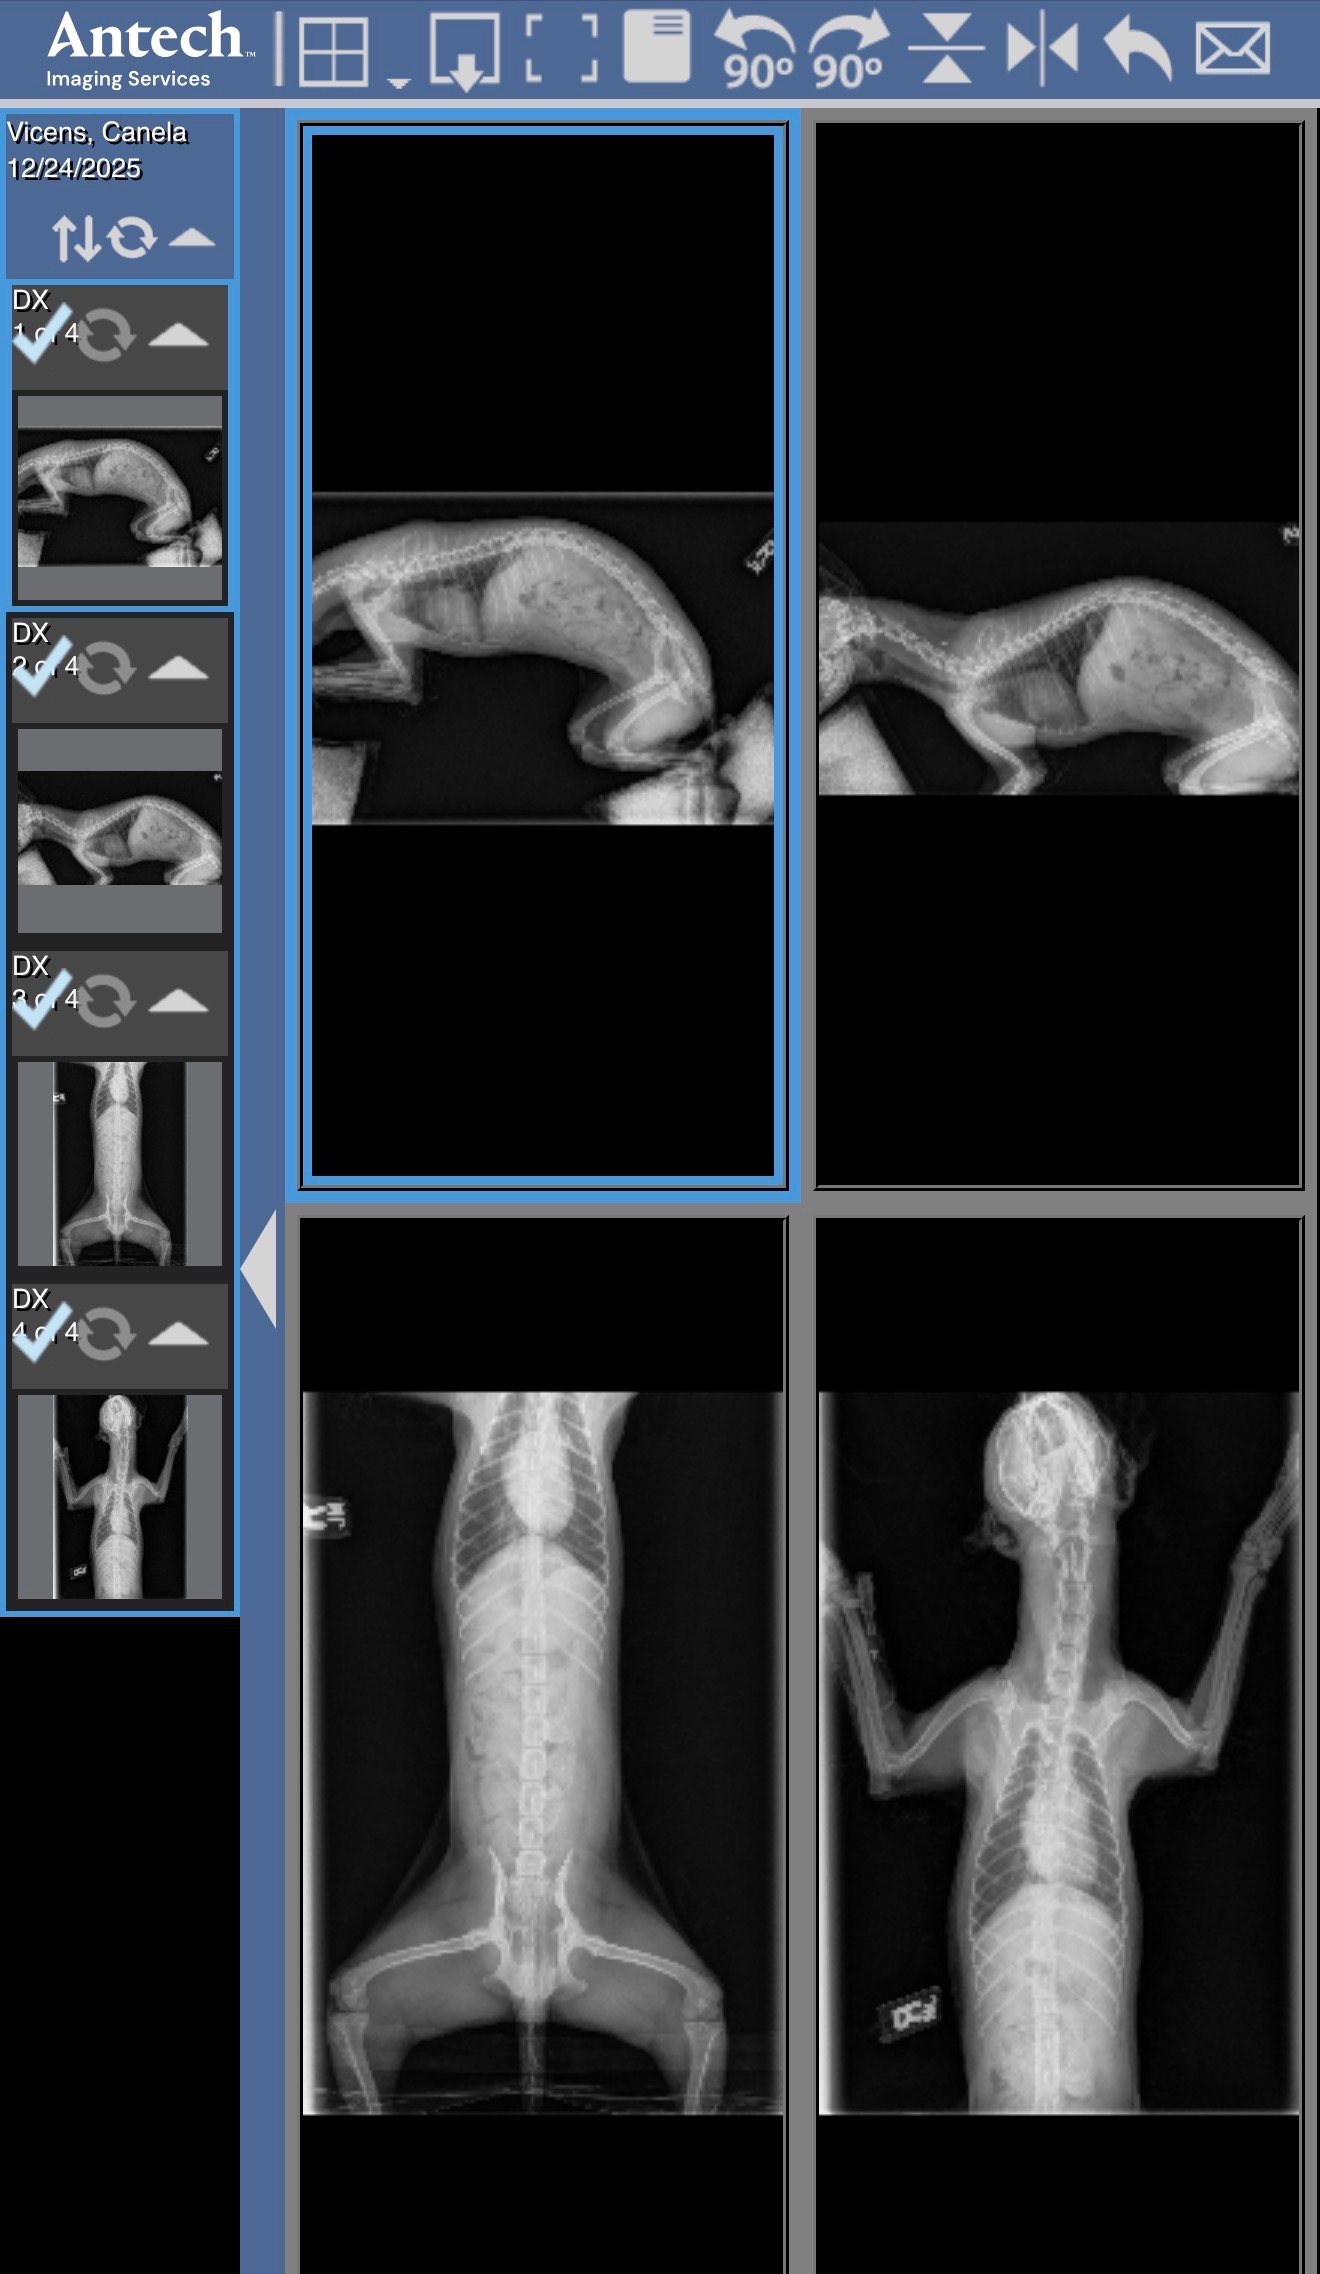

This morning, what was meant to be a joyful day celebrating Christmas with our family turned into a heartbreaking nightmare. Our sweet little dog, Canela, suffered a terrible accident when two heavy celebration tables fell on top of her. The impact caused two fractures in her pelvis, and she was rushed to the emergency veterinary hospital. Canela is currently hospitalized, in pain, and waiting for urgent surgery.